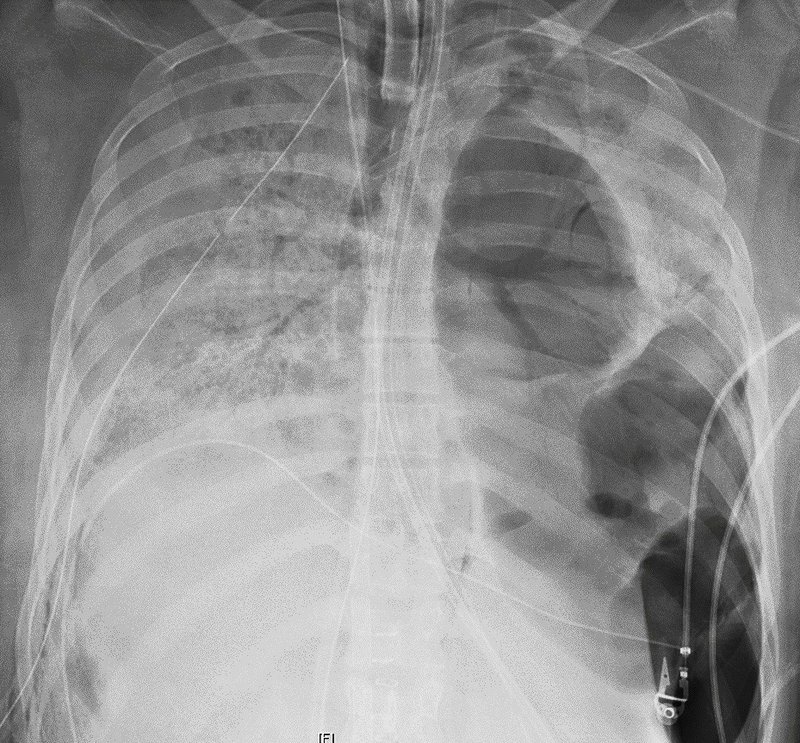

This X-ray image provided by Northwestern Medicine in June 2020 shows the chest of a COVID-19 patient before she received a new set of lungs because of severe lung damage from the coronavirus, at Northwestern Memorial Hospital in Chicago. (Northwestern Medicine via AP)

The 10-hour procedure was challenging because the virus had left her lungs full of holes and almost fused to the chest wall, said Dr. Ankit Bharat, who performed the operation.